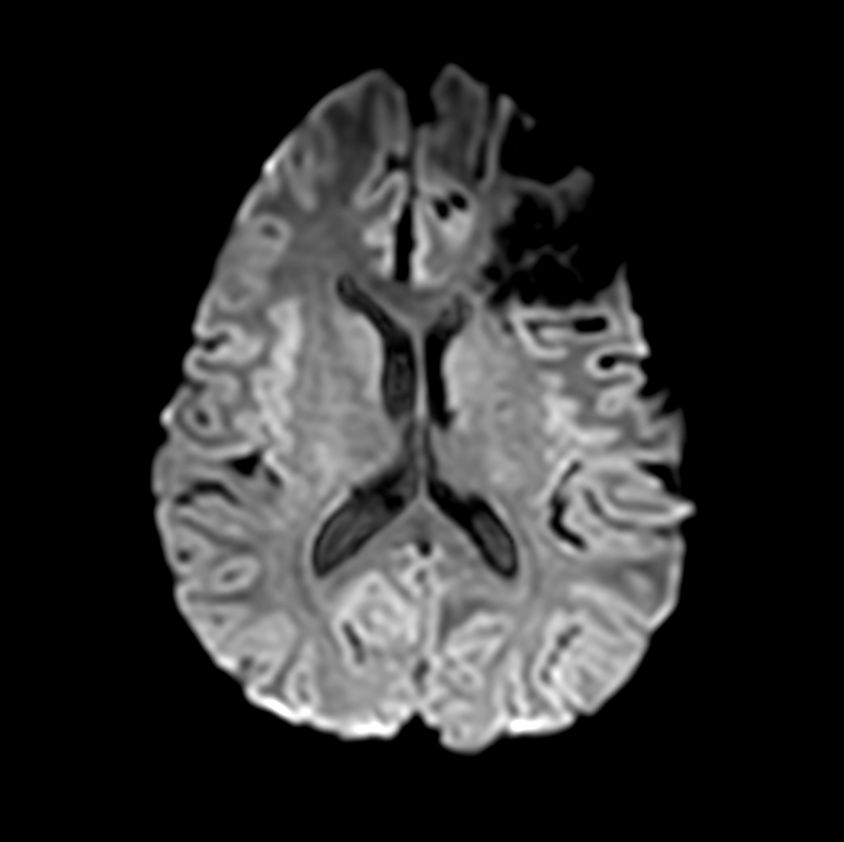

Axial DWI b1000

-